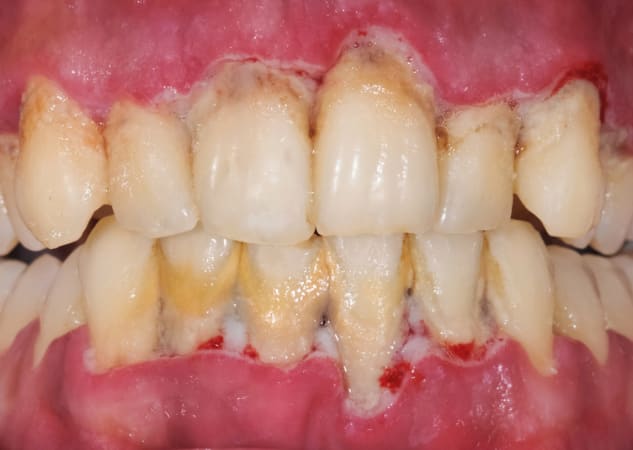

Para que puedas identificarlo visualmente, te ponemos algunas fotos de casos de gingivitis y periodontitis:

Periodontitis